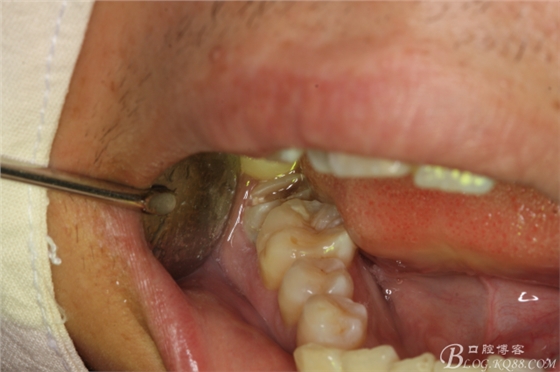

圖9.潛掘法橫斷牙冠

圖10.橫斷牙冠的影像